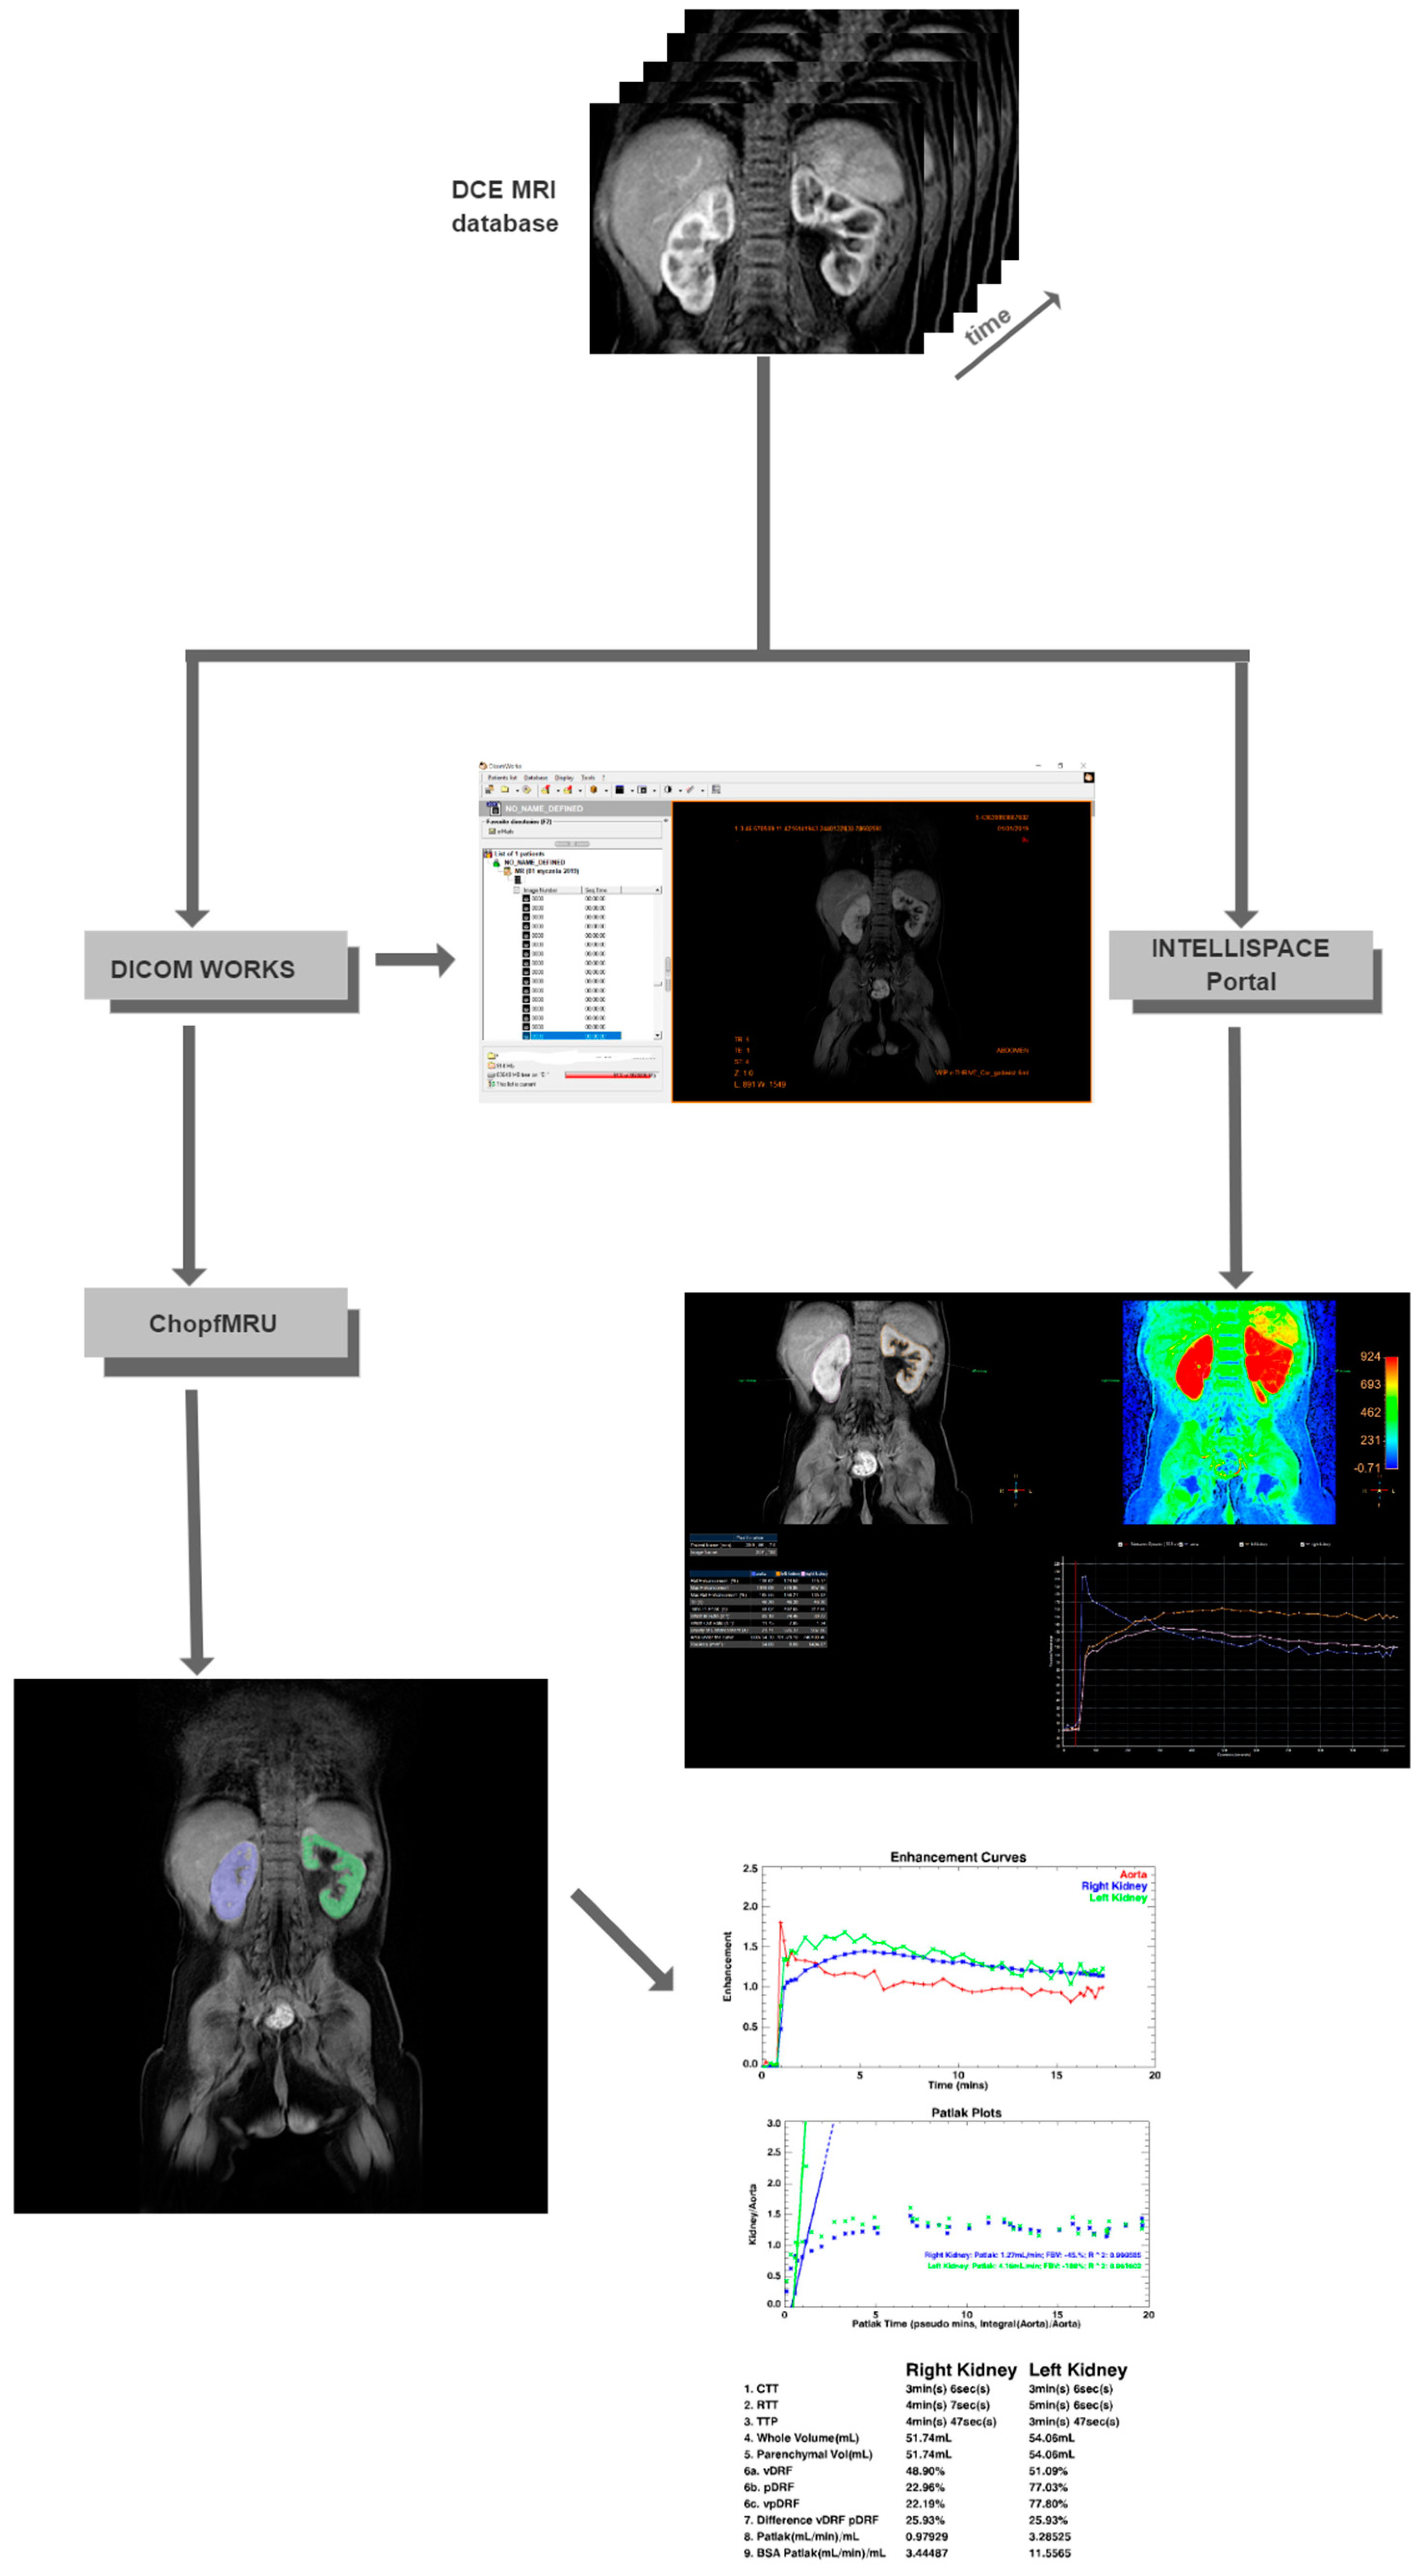

- Separation of the aorta (Figure 3)—the number of time points was found so that the aorta was marked significantly against the background of the organs (the moment of the highest signal intensity in the vessel),

- Separation of the kidneys (Figure 4)—the number of time points was found where contrast is first seen in the calyces,

- Biophysical model analysis (Figure 5)—estimation of functional parameters for the aorta and each kidney.